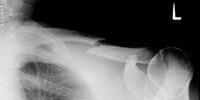

Schlüsselbeinbruch

Gebrochenes Schlüsselbein

Ein Schlüsselbeinbruch ist häufig die Folge von einem Sturz oder Schlag gegen das Schlüsselbein oder die Schulter, zum Beispiel beim Reiten, Fußball oder Skifahren. Dabei kann die bandartige Verbindung vom Schlüsselbein zum Schultergelenk reißen oder das Schlüsselbein brechen. Oft entsteht als Folge eine starke Schwellung und häufig ist eine Stufenbildung in der Schulter sichtbar.

Den Arm in einer Schlinge oder einem Armtragetuch ruhig stellen und einen Transport in das nächste Krankenhaus organisieren.

In den meisten Fällen wird nach der Bruchversorgung für mehrere Wochen ein Rucksackverband angelegt. Krankengymnastische Übungen unterstützen die Heilung. Die Sportfähigkeit ist erst nach Ausheilung des Bruches und Beschwerdefreiheit gegeben.

Eine Operation erfolgt meist nur bei besonderen Bruchformen.